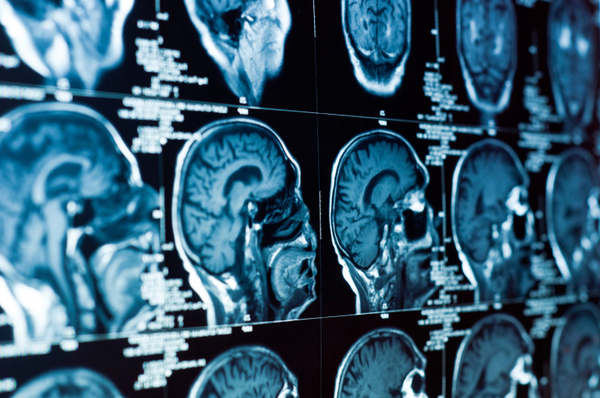

Using powerful microscopes and imaging devices, Rice University researcher Amina Qutub can observe brain cells in a glass container and the connections they make with each other.

Normal brain activity results from those cells — called neurons — linking together in complex networks, and researchers are seeking a better understanding of how that happens.

Brain cells connect with each other through both chemical and electrical signals, and they utilize a variety of proteins to stimulate growth.

In the laboratory there is a piece of abstract art that is composed of images of neuron networks, showing their vast complexity.

"They form very elaborate and beautiful structures," Qutub said of the neurons, "and the different network structures relate to what they do, their function. What we are trying to figure out is what are the chemical signals that lead to a particular structure and, in turn, how does that chemical structure lead to the electrical signals that you get when you have active neurons."